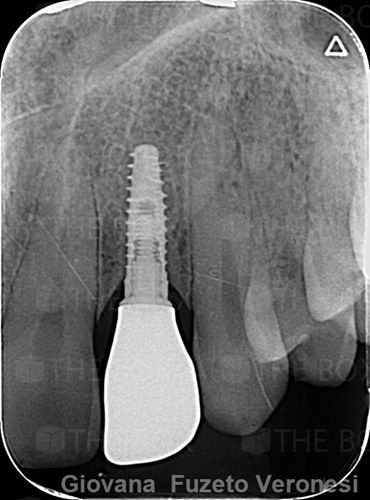

Infra bony defect one wall defect follow up 18 months show regeneration of buccal bone and interdental defect utilizing allograft bone substitute